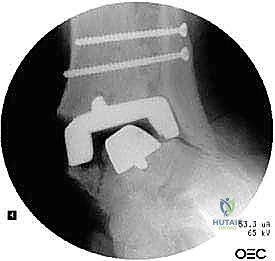

علاج هذه الكسور يتطلب مهارة فائقة من الدكتور محمد هطيف، حيث يتم استخدام تقنيات الجراحة الميكروسكوبية وتثبيت الكسور باستخدام صفائح معدنية دقيقة ومسامير (Locking Plates) دون المساس بثبات المفصل الصناعي، أو يتم دمج علاج الكسر ضمن عملية مراجعة المفصل الكلية إذا كان المفصل نفسه تالفاً.

يتم إدخال المفصل الجديد المخصص للمراجعة، والذي يحتوي غالباً على سيقان (Stems) تدخل عميقاً في عظمة الساق وعظمة الكاحل لضمان الثبات الميكانيكي. في حال وجود كسور في الكعب، يتم تثبيتها في هذه المرحلة.